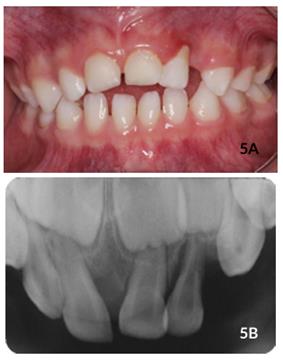

(Figura 4C). Ao acompanhamento de 8 meses, constatou-se que o dente #61 reerupcionou satisfatoriamente apesar de estar ligeiramente acima da linha de oclusão e o paciente apresentar mordida aberta anterior. Novamente, foram observados ausência de inflamação gengival, fístula ou sintomatologia dolorosa (Figura 5A). Além disso, em relação ao dente #62, observou se acúmulo de biofilme dental, vermelhidão e inchaço na gengiva inserida adjacente, com recessão gengival na região cervical devido à interferência oclusal, mobilidade grau I e reabsorção radicular externa (Figura 5B). Ao exame radiográfico, não há sinais de lesões periapicais e lesões periodontais no dente #61. O paciente estava

assintomático e não houve necessidade de intervenção. Ao acompanhamento de 12 meses após o trauma, o paciente retornou com as mesmas características do último atendimento (Figuras 6A e 6B).